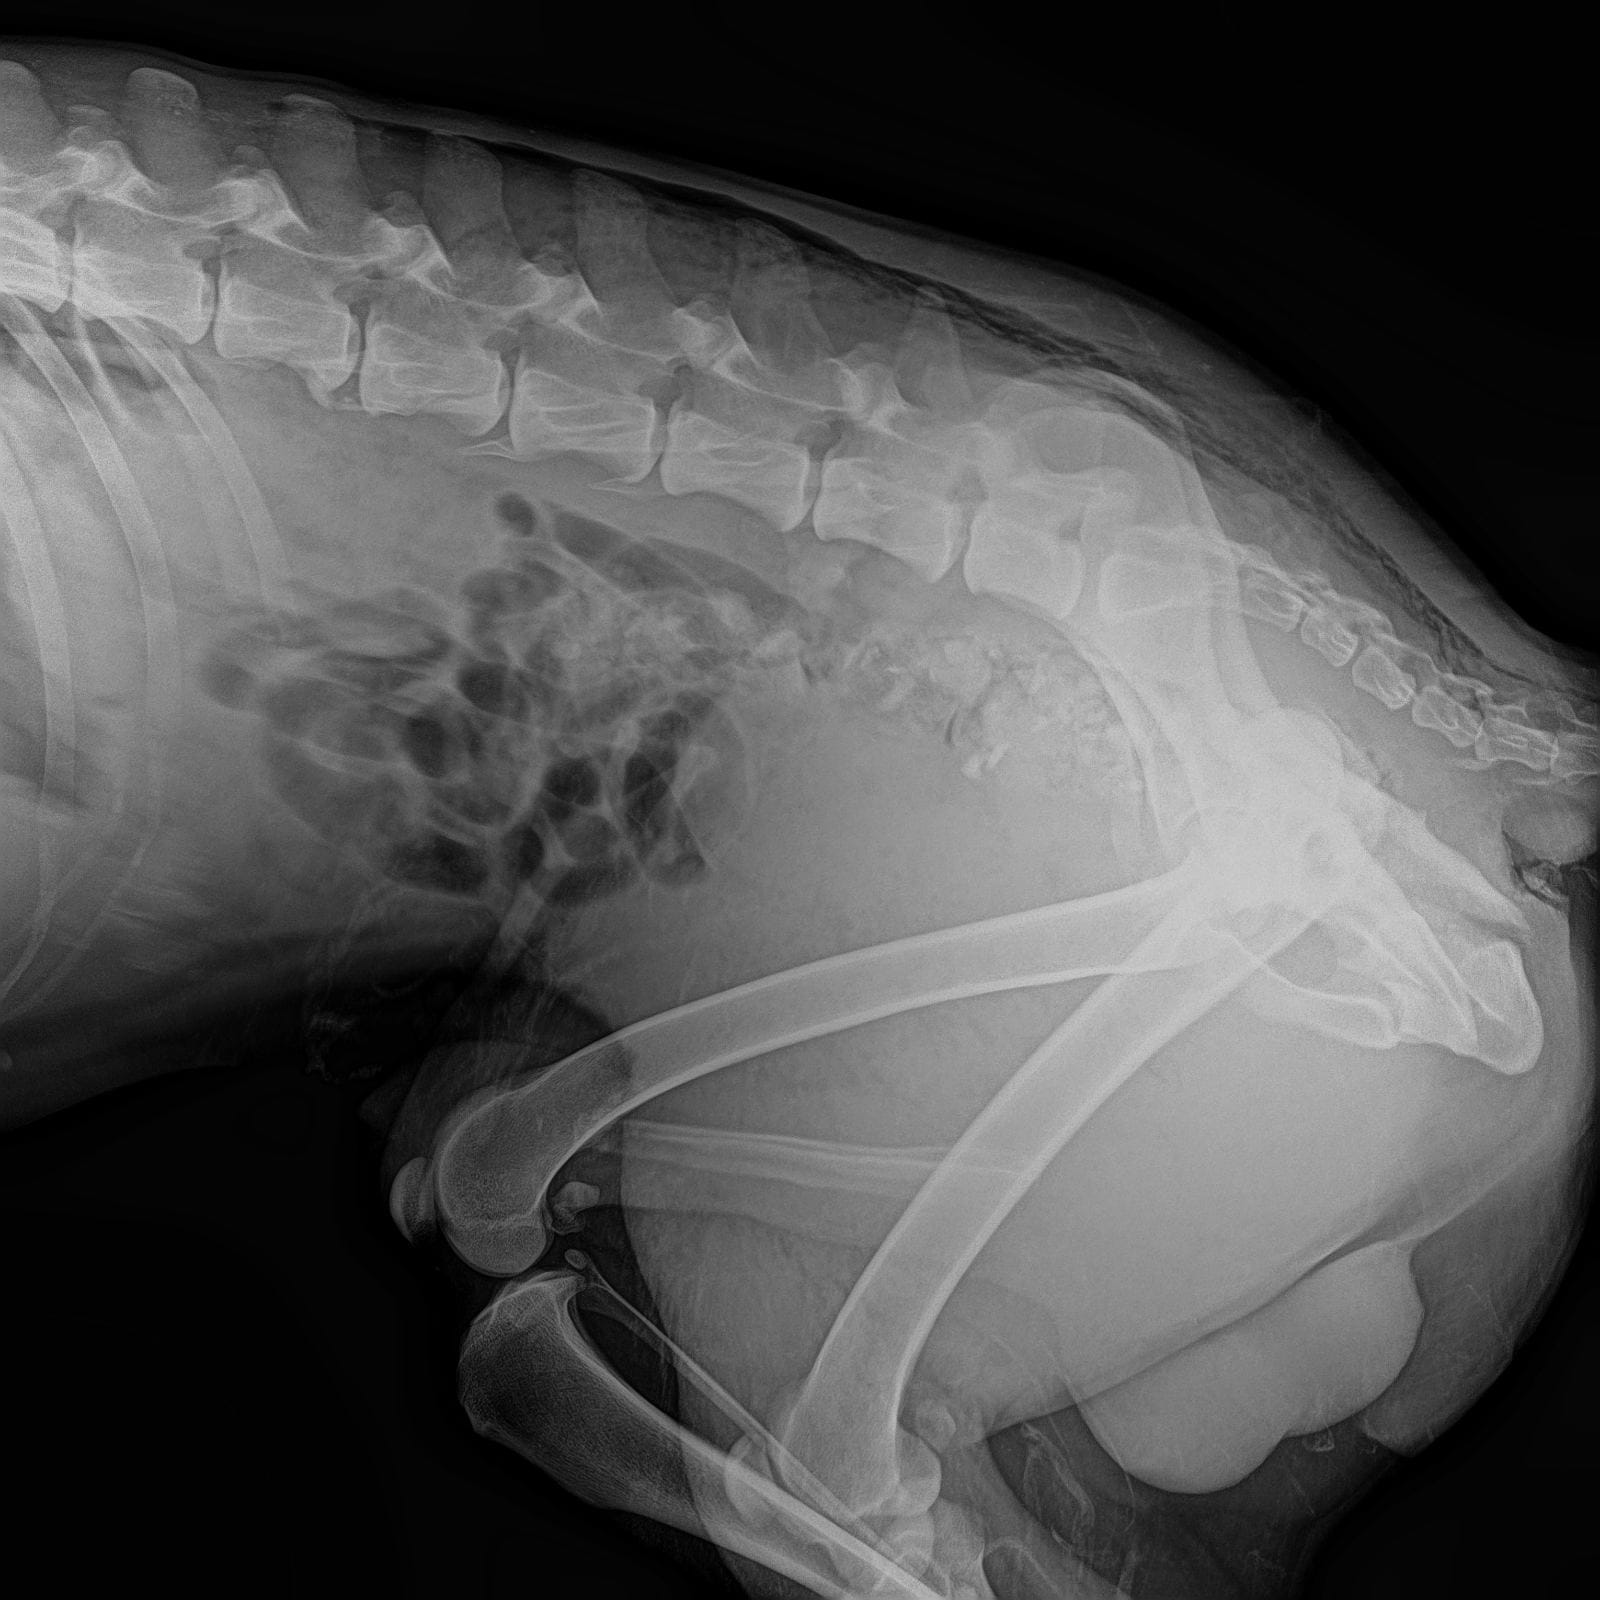

Обследования из клиники Рекс

Выписка из Зоозащиты